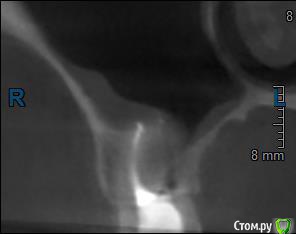

Здравствуйте! Верхний правый шестой зуб пломбировали 3 месяца назад. Примерно месяц назад он начал ныть, после насморка, сначала периодами, а теперь почти постоянно. При постукивание (ощущается не совсем так, как другие зубы) и пальпации десны он не болит. 2,5 месяца назад удаляли кисту из гайморовой пазухи. Может ли быть это какое-то воспаление и есть ли вероятность устранить его какими-нибудь антибиотиками, если да, то как, или может удалить зуб? Если есть воспаление, то какие могут быть последствия если не удалить зуб?

(Снимки с КТ, первые 8(Image) - сделаны сейчас,по 4 в разных проекциях, вторые 8(Before) - сделаны 5 месяцев назад до удаление кисты и повторного пломбирование зуба( до повторного пломбирование он реагировал на горячее, был запломбирован 3 года))